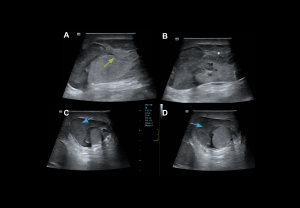

Vascular Disorders

Testicular torsion:

Twisting of the testis around the spermatic cord, leading to vascular compromise.

Types:

- Supravaginal or extravaginal (<5%): Common in neonates

- Intravaginal (≈95%): Associated with the “bell-clapper deformity

Time-sensitive management: testicular salvage is 100% if detorsion occurs within 6 hours, ~75% at 12 hours, and <50% between 12–24 hours.

Clinical features: Sudden pain radiating to the ipsilateral fossae, swelling, absent cremasteric reflex, negative Prehn’s sign, and horizontal orientation.

Grey-scale:

- Early (<6 h): normal echogenicity

- Acute (<6 h): testis enlargement, thickened scrotal coverings, reactive hydrocele, altered epididymal echogenicity or position.

- Late: reduced size, heterogeneous echotexture; hypoechoic areas

Doppler findings:

- Degree of torsion:

- Complete (≥360°): Usually absent intratesticular flow.

- Partial (<360°): Residual intratesticular flow may be detectable.

- Spectral Doppler: Increased resistive index (RI) and possible diastolic flow reversal, whirlpool sign of spermatic cord

- Late (>24 h): Periscrotal hyperaemia reflects inflammation.